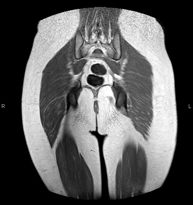

Prova diagnòstica no invasiva que consisteix en l'obtenció d'imatges d'alta definició anatòmica de la pelvis mitjançant l'ús d'un camp electromagnètic i ones de ràdio (amb un emissor i un receptor). No utilitza radiació ionitzant. Es realitza per a l'estudi de patologies d'úter, d'ovari, de trompes i de vagina, ja siguin d'origen tumoral, inflamatori o vascular. També permet valorar les estructures adjacents localitzades a la pelvis i la identificació de les seves alteracions. De vegades és necessari l'ús de contrast intravenós (Gadolini) per caracteritzar les lesions. - RM Pelvis masculina

Prova diagnòstica no invasiva que consisteix en l'obtenció d'imatges d'alta definició anatòmica de la pelvis masculina mitjançant l'ús d'un camp electromagnètic i ones de ràdio (amb un emissor i un receptor). No utilitza radiació ionitzant. No requereix preparació prèvia. En algunes ocasions necessita l'ús de contrast paramagnètic (Gadolini) per caracteritzar les lesions. Aquesta prova permet valorar òrgans com la bufeta urinària, la unió entre els urèters i la bufeta, la pròstata, les vesícules seminals, la uretra i els ossos de la pelvis, entre d'altres. - RM de Fetge

- Hip MRI

Examination for the study of injuries to tendons, muscles and hip joints. Enables early detection of hip osteoarthritis. It is very useful for detecting bursitis and dynamic osteopathy of the pubis, which is common in athletes. It lasts approximately 20 minutes. It is a radiation-free procedure.

- Sacroiliac MRI

Study specifically designed to assess these joints and their inflammation in patients suffering from ankylosing spondylitis. It is also useful in patients with trauma and possible fractures of the sacrum and coccyx. It lasts approximately 16 minutes. It is a radiation-free procedure.

- Gluteal MRI

Examination to study the muscles and tendons that originate at this level, such as the hamstring tendons, which are frequently injured in athletes. It lasts approximately 16 minutes. It is a radiation-free procedure.